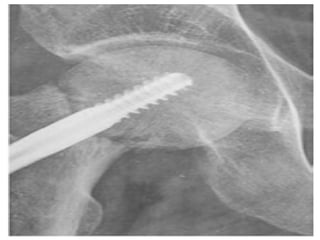

• Screw cut out – mainly following incorrect

placement of screws

• Screw cutout – mainly following incorrect placement of screws